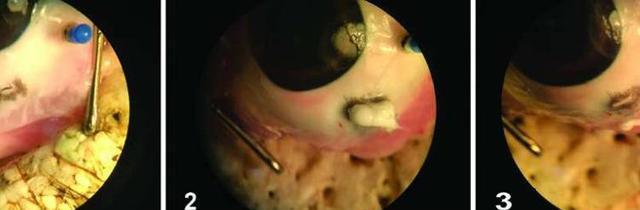

令人欣喜的是,由南加州大學(USC)的科學家和工程師組成的多學科團隊很快就能解決這個問題。他們開發了一種可逆的、熱敏性的臨時密封膠。當應用于眼睛時,該密封膠會從液體轉變為超強的半固體以封住創口。當病人準備好接受手術時,醫生可以通過添加冷水來移除密封膠。該研究結果發表在12月6日的《科學轉化醫學》雜志上。

該研究團隊正研究一種被稱為聚N-異丙基丙烯酰胺(PNIPAM)的水凝膠視網膜植入物材料。它有一個獨特的屬性,并因此十分適合被用于治療眼損傷:當冷卻時,水凝膠變成了一種易于涂抹的液體;而加熱后,它則會變成粘性強的半固體,應用時所需要的只是一些簡單的縫合。

“強效膠水”可封住受傷眼部,為急救贏取時間,降低失明幾率

圖片來源:Science Translational Medicine (2017)

當醫生準備手術時,水凝膠可以通過冷卻水轉化到低粘狀態。

為了確定這種材料的功效,研究人員用一只兔子作為模型。結果表明,將水凝膠涂抹于穿透性眼部損傷時,水凝膠可舒緩眼內的壓力,這可能是防止視網膜脫離并最終導致視力喪失的關鍵。此外,在長達四周的使用中也沒有炎癥或感染的癥狀。研究人員希望在2019年開始對人類進行臨床安全性測試。